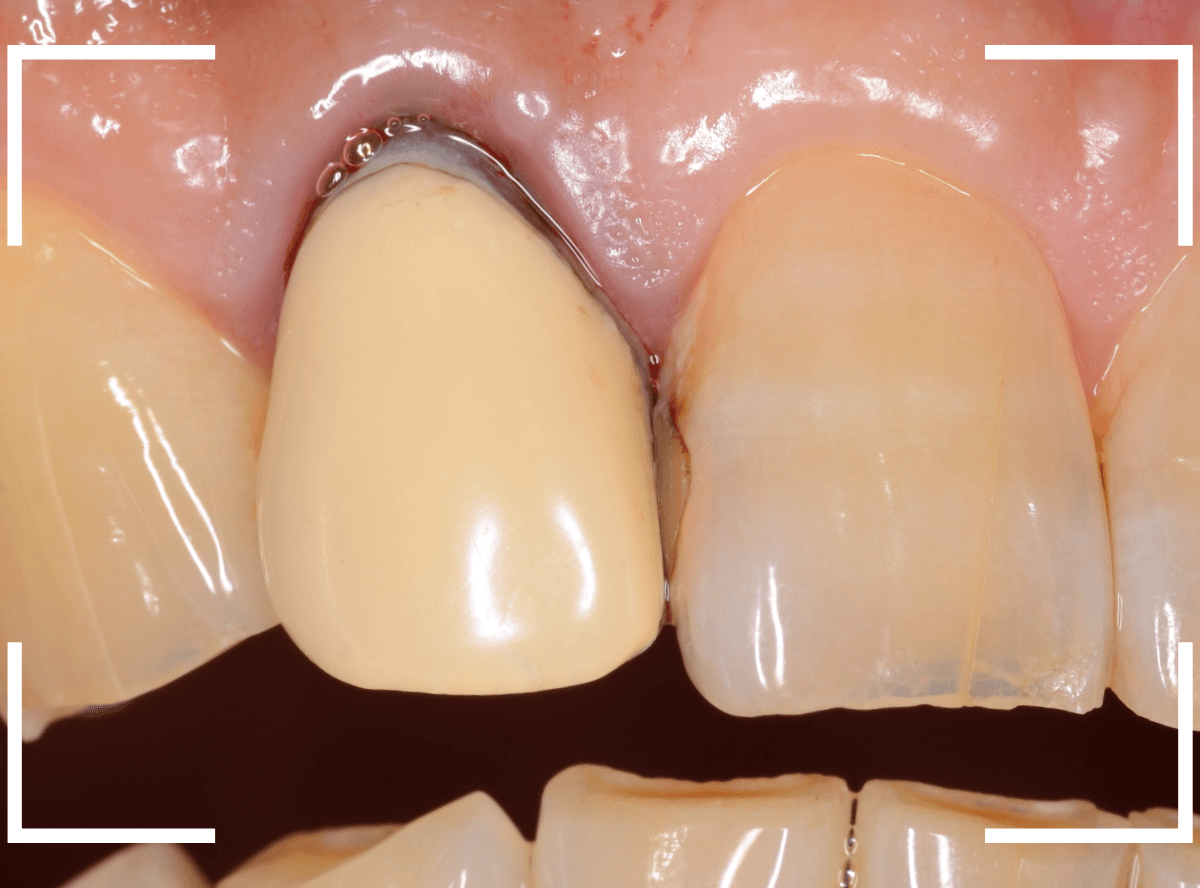

さて、この方の歯の形を確認すると、左右でかなり歯の長さに差があります。

お聞きすると、「若干、そこも気になっていたので、一緒に治療できるならお願いしたい」との事でした。

治療をするためには、歯肉の形をトリミングするなどの若干の外科処置が必要です。

多少の痛みを伴いますが「頑張ります!」との事でしたので、そこも含めて治療する事になりました。

治療のためにさし歯を外すと、隣の歯のレジンの隙間に小さな虫歯が見つかりました。

これはさし歯を外した時あるあるなのですが、一緒に治療をします。

治療をすると、中まで入り込んだ虫歯でしたので、レジンを全て外して治療をし直します。

次に、隣の歯との高さに揃えるために、歯肉をメスで切開して、そこに合わせて歯の形を形成しなおします。